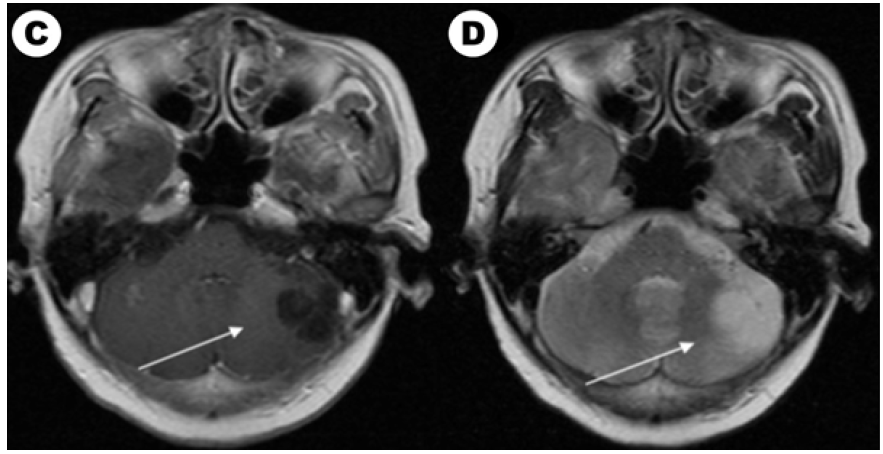

Figure 1A: The brain enhanced MRI of a 61-year-old woman with non-small lung cancer and EGFR 21L858R mutation before and after EGFRTKI treatment. Contrast-enhanced T1-weighted MR image in baseline. Figure 1B: Contrast-enhanced T2-weighted MR image in baseline.

Figure 1C: Contrast-enhanced T1-weighted MR image after EGFR-TKI target therapy and whole brain radiotherapy (the prescription dose and fraction schedule were 30Gy/10F) treatment one month. Figure 1c: Contrast-enhanced T2-weighted MR image after EGFR-TKI target therapy and whole brain radiotherapy treatment one month.

According to our follow-up, 4 patients abandoning therapy and 33 patients which received treatment had evaluable efficacy. Until the last follow-up time, 40 patients had evaluated overall survival and 8 (8/40, 20.0%) patients were still alive. Among them, 14 patients with EGFR/ALK gene mutated had TKI targeted treatment and 19 patients received chemotherapy. For brain radiotherapy, 4 of 14 EGFR/ALK mutated patients received radiotherapy and 12 of 19 patients received chemotherapy had brain radiotherapy. We also compared characteristics between patients received targeted drugs and chemotherapy in (Table 2). We showed a typical case of cystic BM which was EGFR mutated NSCLC patient in (Figure 1A). We showed the baseline brain MRI images in(Figure 1A) (T1-weighted MR image) and(Figure 1C) (T2-weighted MR image). After one month of icotinib-targeted therapy and whole brain radiotherapy, the brain MRI images of the patient presented in (Figure 1C) (T1-weighted MR image) and (Figure 1C) (T2-weighted MR image). The effect+- -+-+-+++-` of this patient showed that the brain lesion had shrunk significantly.